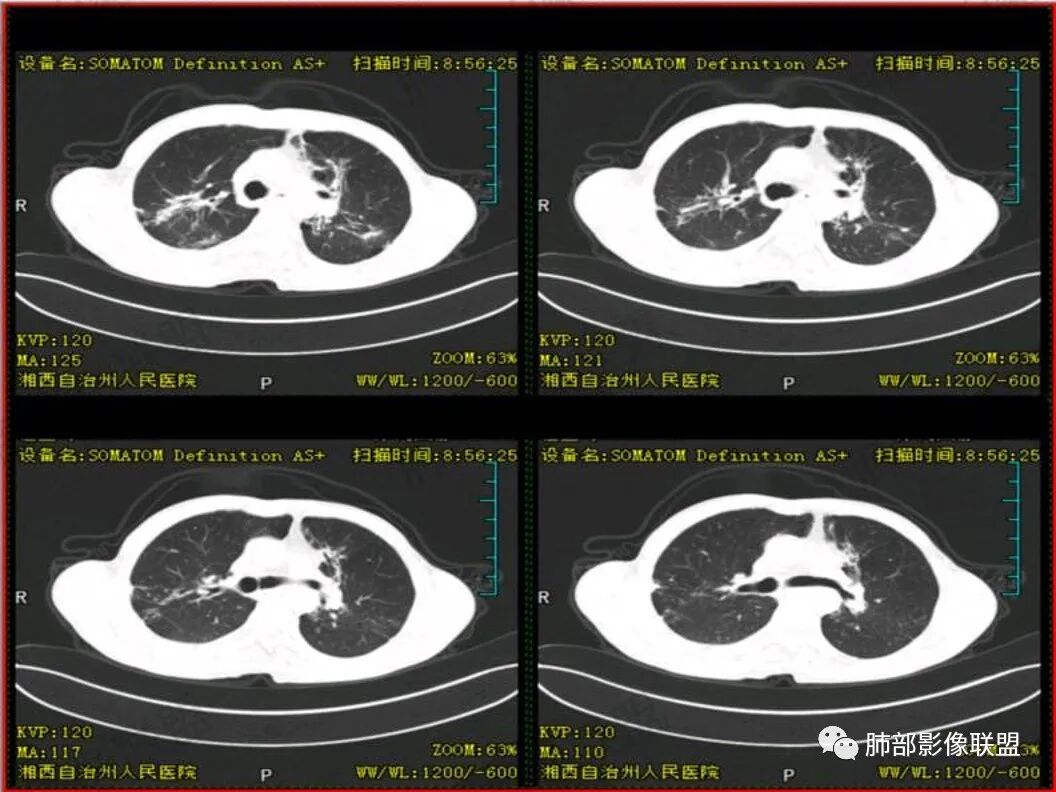

双上肺多发斑片、结节及条索影,边缘清晰,右肺下叶肿块,边缘分叶毛刺,密度不均有坏死,叶间胸膜及侧胸膜牵拉凹陷,斜裂可见六个核桃,周围小叶间隔呈串珠状,纵膈淋巴结肿大坏死,边缘可见钙化,考虑双肺结核,右下肺腺癌。鉴别鳞癌。

患者中年男性,以咳嗽 胸痛就诊

既往有肺结核病史

胸CT可见右肺下叶前基底段占位性病变,病灶周围可见周围不清毛玻璃影,病灶边缘可见分叶,呈膨胀性生长,纵隔窗可见病灶内呈偏心性坏死,增强扫描静脉期强于动脉期,纵隔隆突下淋巴结可见肿大坏死。

诊断考虑肺结核合并肺癌?

男性,咳嗽咳痰,无发热,以往结核并治疗中,两肺有结核背景,淋巴结增大钙化,右肺下叶病灶边缘模糊,内部坏死,坏死区边缘光整,实性部分强化均匀,血管通过截断

诊断:双肺tb+右肺下叶肺癌(鳞癌>腺癌)

双肺肺气肿伴纤维索条,结节影,以双上肺为主,部分可见支气管扩张,右肺下叶实性肿块,边缘毛糙,病灶较密实,支气管堵塞可能?平扫密度尚可,增强后不均匀强化,叶裂可见多个结节影,纵隔淋巴结肿大,考虑:肺癌伴陈旧性肺结核,肺脓肿伴陈旧性结核

双肺上叶多态,多灶,支持结核。右肺下叶肿块,边缘模糊,毛刺,胸膜牵拉,中央坏死,不均匀强化,似乎有壁结节,斜裂增厚,纵隔淋巴结肿大,二元,结核+鳞。鉴别结核+曲霉。

双上肺多发病灶,考虑结核(陈旧灶为主),右肺下叶前基底段占位,分叶、毛刺、胸膜牵拉,中央坏死,局部壁不光滑,前基底段支气管未见显示,不均匀强化,病灶远端阻塞性炎症,纵隔淋巴结肿大、融合。综合考虑恶性病变,鳞癌可能大。

双上肺多发条索及斑片状,局部支气管扩张,考虑结核。右下肺病灶分叶毛刺,胸膜牵拉,不均匀强化,坏死。纵隔淋巴结肿大,坏死,考虑右下肺肺癌并淋巴结转移,鳞癌可能。

中年男性,双肺多形性病变,双上肺纤维条索影及片状影,右肺下叶团块,有分叶,胸膜牵拉,毛刺,增强示坏死明显,坏死边界较清,也可能是容积效应,周围卫星灶,目测没看到明显支气管堵塞,一元考虑结核,二元考虑结核合并恶性肿瘤(鳞癌?)

临床 中年男性,咳嗽盗汗、老结核史,血沉高、t试验阳性,结核应该存在,cyf高4倍,价值怎么样待验证。影像 :两上肺实变加粗大索条灶,两肺野弥漫粟粒,考虑结核应该问题不大。重点分析右下病灶:隆突下淋巴结肿大,但伴钙化,有边缘强化?淋巴结融合又是恶性征像?右下肺病灶冠状位总体方正,横断位总体三角型,长毛刺、近端也有渗出、坏死彻底、空洞壁光滑锐利,似有边缘强化?看做薄壁空洞?以上符合炎性病灶。   支持恶性的征像 :冠状位的空洞似有壁结节,偏心坏死。   综合 ,右下肺鳞癌(偏心空洞+cfy)+两肺结核。

中年男,既往结核,慢性病程,有炎症指标增高和中毒症状。ct双肺上叶索条牵拉支扩伴有树丫,考虑陈旧性结核。

右下叶前基地段肿块,不规则边缘,周围树丫和长短毛刺,内部小空泡,强化后环形强化,纵膈淋巴结肿大,并有不规则环形强化和钙化,总体考虑感染性病变,结核病。

右下叶肿块鳞癌待除外。